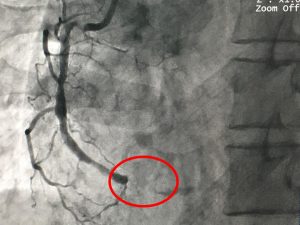

Ngày 10/8/2017, Khoa Phẫu thuật Tim Mạch và Lồng Ngực tại Bệnh Viện Đa Khoa Xuyên Á (BVXA) tiếp nhận phẫu thuật cấp cứu cho bệnh nhân N.T.T.H (sinh năm 1938 ngụ tại H. Đức Hòa, Tỉnh Long An) bị tắc mạch chân trái cấp tính. Trước đó 3 ngày, bệnh nhân H. nhập viện […]